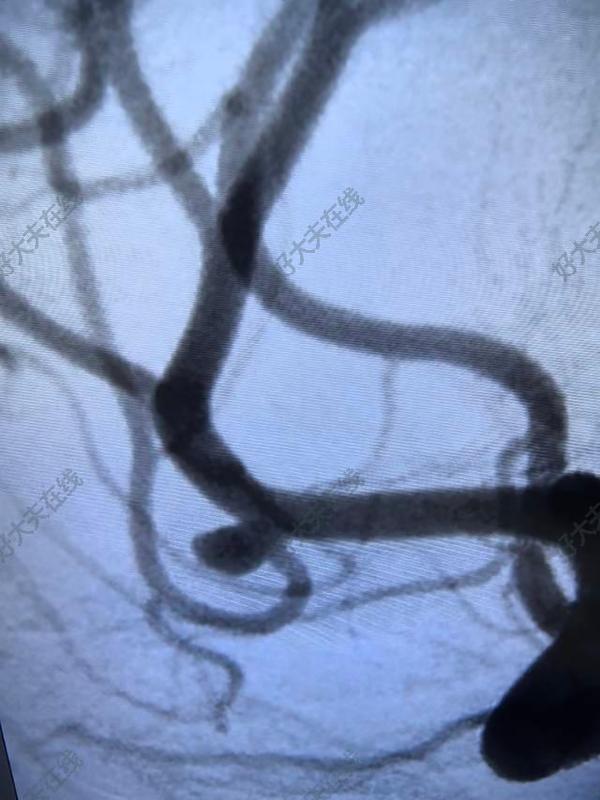

大腦中動脈瘤

治療前檢查發(fā)現(xiàn),但動脈瘤位于大腦中動脈,出血風(fēng)險高,建議治療,微創(chuàng)介入優(yōu)先考慮治療中治療的難點在于下面分支的保護,大腦中動脈瘤的治療我們一共有6種不同的治療策略,我們選擇了支架輔助,關(guān)鍵是術(shù)中彈簧圈的調(diào)整對術(shù)者要求高治療后治療后即刻手術(shù)順利,分支通暢,患者無不適